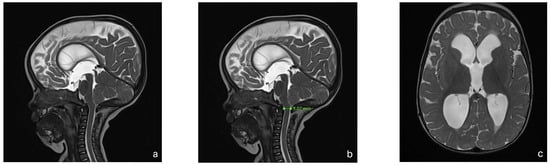

With this standardized procedural sedation approach and continuous multimodal monitoring, none of the patients required endotracheal intubation or a laryngeal mask airway. All MRI scans were reviewed by a board-certified pediatric radiologist and deemed of sufficient quality for diagnostic purposes. No repeat imaging was required due to motion artifacts. Figure 2 presents a representative MRI image acquired under the standardized sedation protocol.

Figure 2.

MRI of an 8-month-old child with achondroplasia. (a) Sagittal T2-weighted magnetic resonance image (MRI) shows foramen magnum stenosis with normal signal in the cervical spinal cord. (b) Sagittal T2-weighted MRI highlights a reduced dens–opisthion distance, with the anteroposterior diameter at the C2–C0 level measuring 9 mm. (c) Axial T2-weighted MRI shows ventriculomegaly. (d) Sagittal T2-weighted SPACE image demonstrates reduced perimedullary cerebrospinal fluid (CSF) flow void signal at the cervicocranial junction. (e) Sagittal T1-weighted image shows no evidence of cerebellar tonsillar herniation. (f) Sagittal T2-weighted FLAIR image shows no signs of cervical myelopathy.